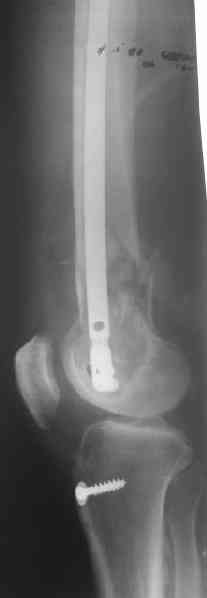

Удалили ластину без проблем. Выявилась значительная подвижность. В этих условиях сразу пропала мотивация к постепенной коррекции аппаратом. Попробовал восстановить длину, введя между отломками spreader. Отчасти удалось. Тогда защили рану, наложили спицевой дистрактор (2 спицы в дистальный отдел и 1 вверху). после этого был убран и спонгиозный винт. И сделали антгерадное штифтование, как говорится, "по принятой в

клинике методике".

Дополнительные доступы для введения гвоздя и проксимальных винтов понадобились, но они маленькие, по 1 см. Нижние винты ввели прямо между швами. Суставы дополнительно не травмировали, и даже ввели гвоздь не через f. piriformis, а через большой вертел.

Длину восстановили, возможно, даже с изьбытком, ну да динамизируем пораньше. Введенные в овальное отверстие дистальые винты имеют угловую стабильность. Снимки приложены. Заранее спасибо за критику и комментарии.

Довольно симпатично получилось. Не сомневался, что будет именно такой антеградный реостеосинтез.

This is a worst site for non-union.

Bone grafting could have been done at reoperation.